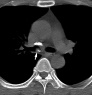

A42 Актиномикоз